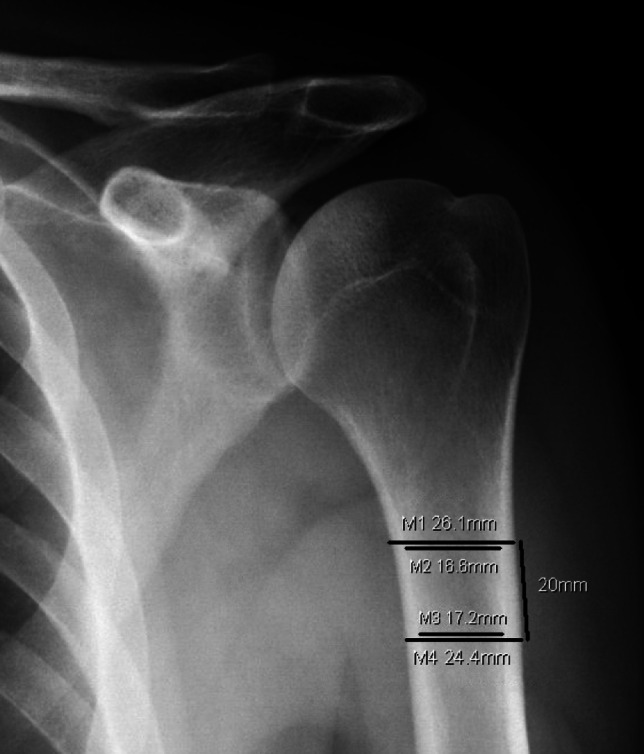

Recent findings: Emerging data surrounding perioperative use of anti-osteoporosis medications for patients undergoing shoulder surgery have not shown definitively favorable or unfavorable outcomes. Similar evaluations in animal studies have shown promising results as a biologic augment to tendon and bone healing, especially with newer, anabolic agents. The mainstay of bone health management remains pre-operative evaluation, using opportunistic radiographic and CT based validated measurements, along with optimization of risk factors. Surgical techniques continue to incorporate implants that perform well in osteopenic bone. Promising pre-clinical studies have identified anabolic anti-osteoporosis medications as viable biologic augments to shoulder surgery, which has not been borne out in any clinical studies at this time.